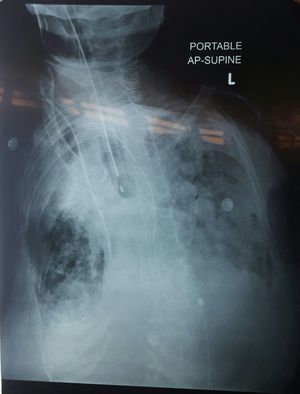

78yrs old lady admitted for CAP (multilobar pneumonia) with hx of COPD